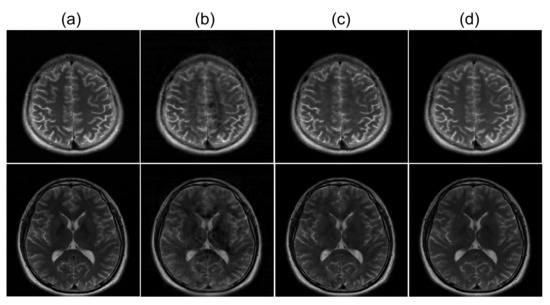

4.2. Acceleration with a Single-Channel RF Coil

While most parallel MRI methods utilize information from multi-channel RF coils to reconstruct images from undersampled k-space data, deep learning-based reconstruction approaches can generate unaliased images from an undersampled dataset without using the information of the multi-channel receive coil [40]. To demonstrate the performance of the proposed ETER-net, we performed image reconstruction from the undersampled k-space data obtained with a single receive channel. To compare the results with a commonly used deep learning reconstruction method, we also simulated the image-domain to image-domain reconstruction using the dual frame U-net. In this experiment, the label images were reconstructed from fully sampled k-space data of a single receive channel. Figure 6 shows three different slices reconstructed from a single channel k-space data, which were undersampled with a reduction factor of four. All images show non-uniform intensities because the k-space data are acquired from a single receive channel, which has non-uniform sensitivity. The images reconstructed by the DFU (column (b)) and the ETER-net (column (d)) are very similar to the label images in column (a). However, when the images are brightened to emphasize artifacts (columns (c) and (e)), it is clear that the proposed ETER-net generates images with less artifacts than the DFU. In particular, the images reconstructed by the DFU have more blurred structural edges and apparent aliasing artifacts, while the ETER-net generates alias-free images with improved image details.

Figure 6.

Images reconstructed from a single channel k-space data, which are undersampled with a reduction factor of four: (a): label images, (b,c): images reconstructed by the DFU and the corresponding brightened images, (d,e): images reconstructed by the ETER-net and the corresponding brightened images. Brightening was performed by taking the root of each value in the image.